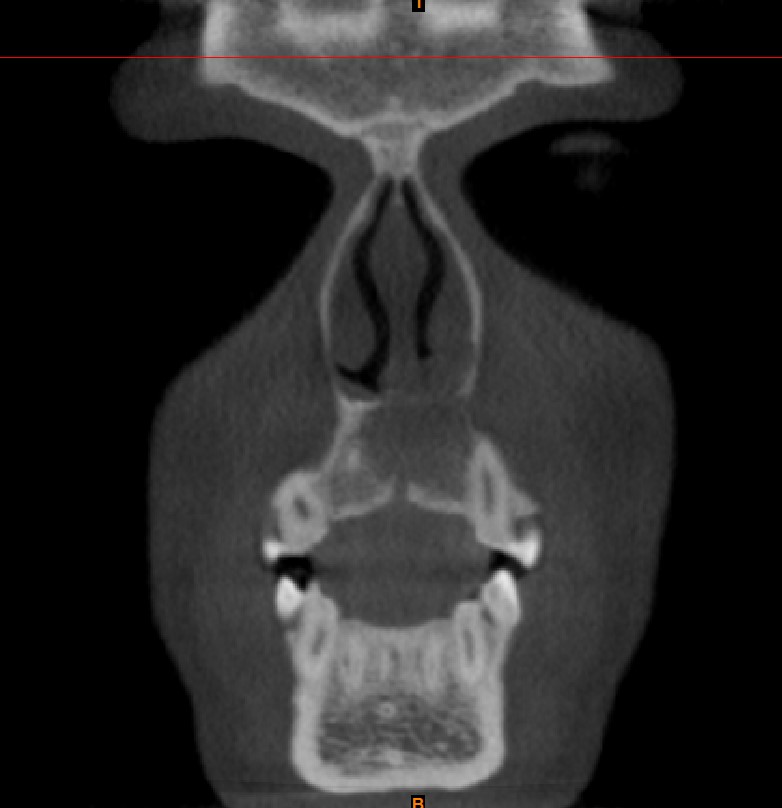

Radiological findings

• CBCT showing well defined unilocular radiolucency with cortical destruction present in anterior maxilla